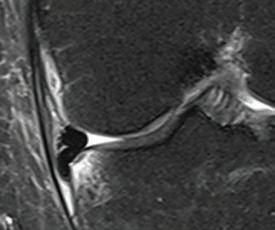

the line? Dr David Colvin 52 Imaging of the knee Dr Gavin Watson 55 Shoulder instability surgery: do it right, do it once Dr William Blakeney 61 A new health paradigm Dr

Rotator cuff repair – where do we draw